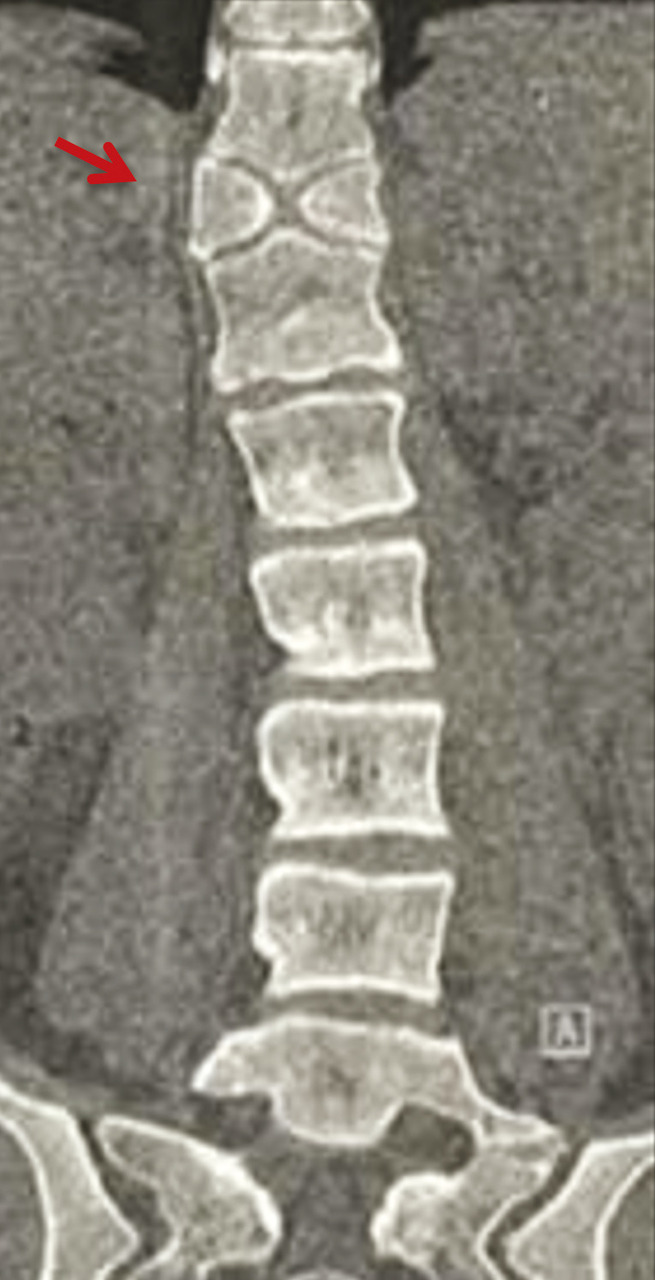

Une patiente de 25 ans, sans antécédents pathologiques particuliers, consulte pour des dorsolombalgies mécaniques avec une irradiation intercostale, sans déficit moteur ou sensitif. L’examen clinique met en évidence une hypercyphose dorsale et une hyperlordose lombaire. Les scanners dorsolombaires (fig. 1 et 2) objectivent une division complète du corps vertébral D11 en hémivertèbre dite « en aile de papillon ». La patiente est mise sous traitement symptomatique associé au renforcement des muscles paravertébraux et respiratoires avec une bonne évolution.

Les vertèbres papillon sont secondaires à un défaut de fusion du corps vertébral plus ou moins étendu au cours de l’embryogenèse.1 Cette anomalie du développement, qui implique généralement une seule vertèbre, peut induire une division complète du corps vertébral en deux hémivertèbres de forme triangulaire. Elles sont souvent asymptomatiques et détectées accidentellement.1 La concomitance entre les vertèbres papillon et les maladies congénitales telles que les syndromes d’Alagille, de Jarcho-Levin, de Crouzon et de Pfeiffer, est parfois constatée. En raison de leur rareté, elles peuvent facilement être confondues à tort avec d’autres processus pathologiques, notamment une fracture vertébrale.

Les deux moitiés sont généralement égales mais peuvent être asymétriques, avec un arc postérieur et des pédicules intacts.4,5 Dans certains cas, ils peuvent être reliés par un isthme osseux.6 L’anomalie de la statique vertébrale est associée dans 70 % des cas, la scoliose étant la découverte la plus courante.2

La colonne vertébrale thoracolombaire est le site le plus fréquent pour la formation des vertèbres papillon.4,7,8 Le siège préférentiel d’une vertèbre papillon unique est T1 et T11.2,7

Il est important de comprendre les caractéristiques radiographiques des vertèbres papillon pour les distinguer des autres processus pathologiques (fracture, métastase, syringomyélie et maladie de Charcot). Un examen attentif des vertèbres adjacentes montre des caractéristiques de déformation de longue date, telles qu’un allongement exagéré des marges antérieures et un disque intervertébral normal. De plus, les vertèbres papillon causent généralement moins de cyphose. Plusieurs publications ont établi un lien entre les vertèbres papillon et les lombalgies1,9,10 dont le traitement est généralement conservateur. La cause de la lombalgie chez un patient avec des vertèbres papillon peut être sans rapport avec l’anomalie structurale et nécessite donc des recherches supplémentaires. Cependant, le traitement de la lombalgie dans la plupart des cas est généralement conservateur.